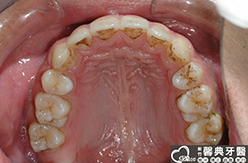

患者︰趙同學,20多歲,學生。

主訴︰齒列不正,暴牙,不好看。

治療計劃︰上下顎齒列平整、後縮,重建正常咬合關係。

上、下顎前突,俗稱暴牙,由於上下前牙向前暴出,在外觀上容易產生牙齒外露的現象,雙唇較難自然閉合,嘴唇看也來也會比較厚。